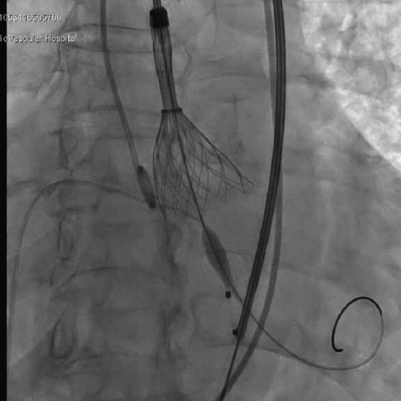

右窦中心位 标准位释放瓣膜

人工瓣膜位置、形态良好,无反流

术中,先对人工瓣膜进行定位,到达预期位置后精准释放,手术结果令人满意。